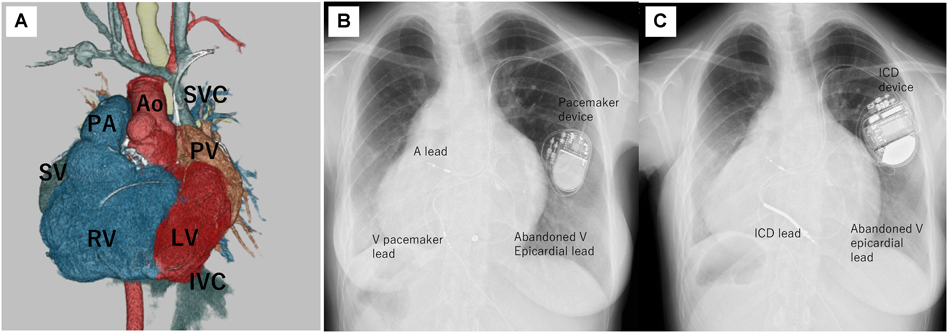

Fig. 2 Adult women repaired tetralogy of Fallot with sustained ventricular tachycardia and residual atrial shunt. She underwent atrial septal defect closure using atrial septal defect occluder before transvenous ICD implantation to prevent lead related systemic thrombosis

A: Chest X-ray (frontal view). B: Chest X-ray (lateral view). White arrow: atrial septal defect occluder. ICD, implantable cardioverter defibrillator

Fig. 3 CRT using transvenous ICD combined with epicardial lead on systemic right ventricle in a patient underwent Senning operation for TGA, complete atrioventricular block and systemic ventricle failure

A: 3D CT image of all chamber. B: 3D CT image of systemic venous chamber. C: 3D CT image of subpulmonary ventricle and pulmonary artery. D: Chest X-ray (frontal view). E: Chest X-ray (lateral view). A lead, atrial lead; Ao, aorta; Epi lead, epicardial lead; ICD, implantable cardioverter defibrillator; LAA, left atrial appendage; LV, left ventricle; MV, mitral valve; PA, pulmonary artery; RV, right ventricle; SVC, superior vena cava; TGA, transposition of great arteries